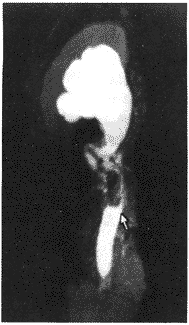

磁共振尿路成像在输尿管肿瘤诊断中的应用价值

磁共振尿路成像(MRU)是检查上尿路的一种新方法 ......